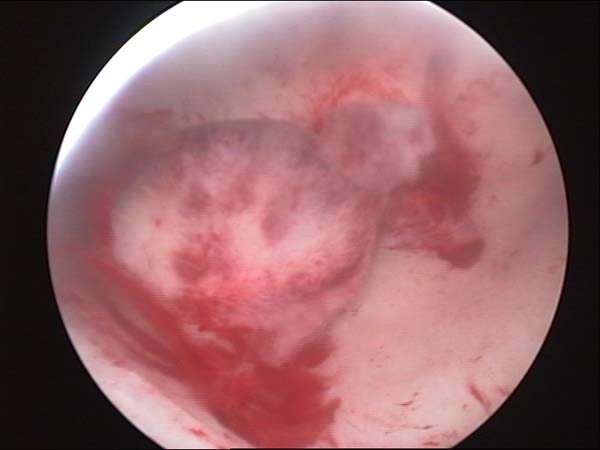

- Hysteroscopy Video clips

- Hysteroscopy Photos

Hysteroscopy Pictures | Dr N Layyous